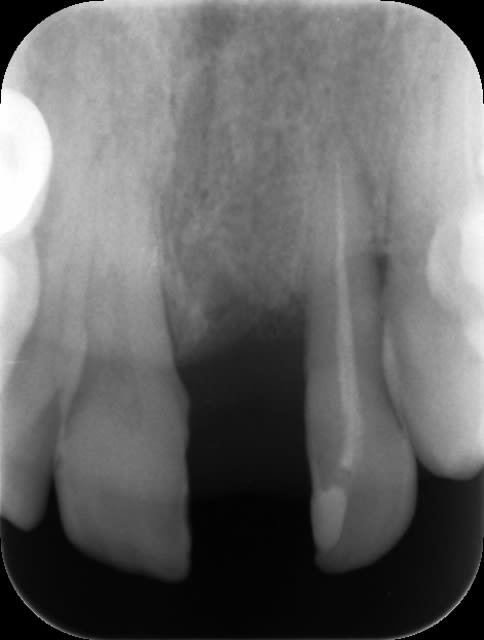

est ce qu'un implant peut trouver sa place ici ? alors quel serait l'avenir de la 22

sinon est ce qu'un bridge est preferable la solution implantaire et quels piliers choisir ?

A priori on peut toujours poser un implant dans ton cas.

Le probleme viendra plus de la recession tissulaire qui entrainera la fabrication d'une ccm "longue" ce qui peut etre disgracieux si le patient a une ligne du sourire haut placee.

Idem pour les diastemes interproximaux.

Ne fais pas de bridge car c'est enterrer les collaterales...

avant tout il faut déjà voir le volume osseux que tu as (scann) si tout est ok la pose d'1 implant est tout à fait jouable, aprés en effet tu vas avoir un soucis de hauteur de couronne.

2 solutions : soit lors de la pose en profiter pour réaliser une greffe ggvale, mais qui ne suffira peut être pas

ou alors lors de la réalisation de la couronne tu fait une céram ggvale ( rose ) pour aligner les collet, le résultat est pas mal.

pour la latérale il faut + d'info?